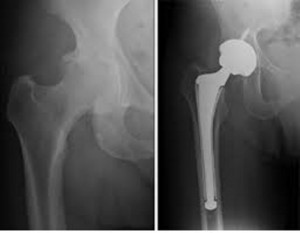

Η χειρουργική αντιμετώπιση περιλαμβάνει τον αρθροσκοπικό καθαρισμό της άρθρωσης, που μπορεί να καθυστερήσει την αρθροπλαστική για μερικά έτη, και εφαρμόζεται με τοπική αναισθησία , ανώδυνα χωρίς να χρειάζεται νοσηλεία στο νοσοκομείο (day surgery).. Η οριστική χειρουργική αντιμετώπιση της οστεοαρθρίτιδας του γόνατος γίνεται με την ολική αρθροπλαστική, κατά την οποία αφαιρούνται τμήματα της άρθρωσης που είναι κατεστραμμένα από την οστεοαρθρίτιδα και αντικαθίστανται με τεχνητή άρθρωση, φτιαγμένη από συνθετικό υλικό.